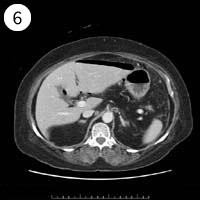

57歳 女性

単純CT

造影CT